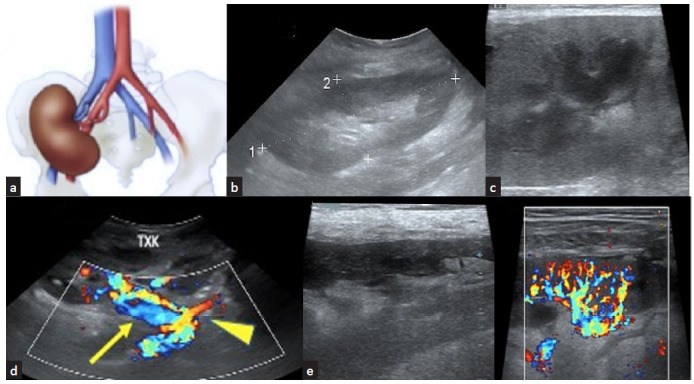

Point of care ultrasound (POCUS) is gaining wide recognition in its bedside applications. The day-to-day practice of nephrology requires several ultrasonographic parameters for diagnosis. Hence, familiarity with basics of renal ultrasound imaging is becoming a necessary skill for every nephrologist. This review provides an overview of the normal and abnormal findings in a graft kidney and its environment throughout graft survival and after its failure. The correlative understanding of the clinical features with image findings provides the greatest advantage in applying POCUS at the bedside.

Abstract Image